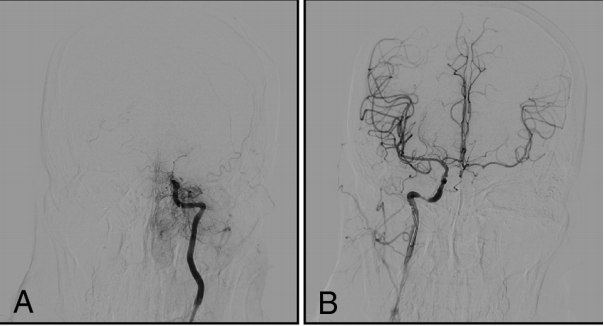

图4. 男性患者,左侧肢体无力20天。A和B,DSA显示右侧颈内动脉颅内段闭塞,闭塞长度不确定,AcomA或PcomA无代偿(III型);C,微导丝与微导管结合,穿过闭塞节段;D,再通成功。

对于III型病变,本研究显示其再通率较低(50%),围手术期并发症发生率较高(50%)。由于AcomA或PcomA有或无、闭塞长度和过程的不确定性显著增加了血管内再通的手术风险,III型患者血管穿孔等手术相关并发症的发生率明显增高,这可能提示血管内再通手术应谨慎进行。实际上,在III型中,远端侧支代偿主要来自大脑中动脉和大脑后动脉或大脑后动脉之间的软脑膜吻合,血管造影可能显示远端MCA M1主干或M2-3分支的逆行血流。根据不同的远端侧支代偿,III型可分为亚型a和b:在亚型a中,可在远端MCA M1主干远端可看到血流的逆行充盈。在亚型b中,仅在M2–3分支远端中可见血流逆行充盈。由于样本量较小,我们没有单独的统计分析。值得进一步研究大数据研究。